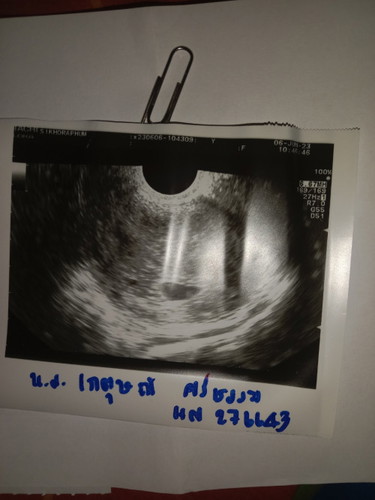

ยังไม่เห็นตัวเด็ก

คือวันนี้เราไปฝากท้อง แต่ไม่เจอตัวเด็กท้องได้5 สัปดาห์4วัน หมอนัดอีกที วันที่20 มิ.ย มีโอกาสจะเจอมั้ยค่ะ หรือน้องยังเล็กถึงไม่เห็นค่ะ มีโอกาศจะเจอน้อยมั้ยค่ะบ้าง เครียดมากเลยค่ะ

ต้องรออีกสัก 2 สัปดาห์ค่ะแม่ เราซาวด์ทางช่องคลอดเจอน้องตอน 6wk2d

น้องยังตัวอยู่เลยค่ะ